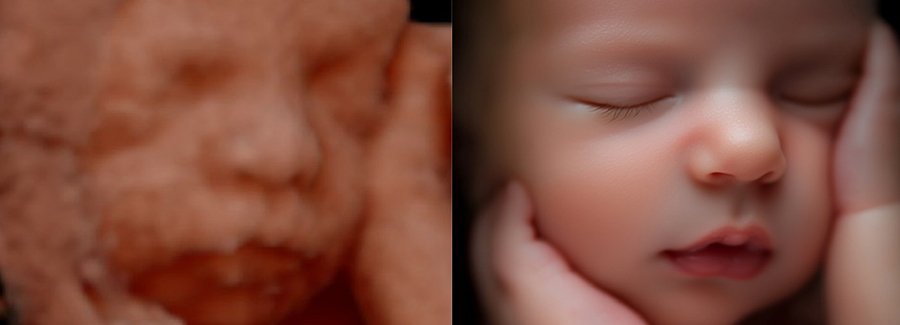

The best time to see your baby’s face in 5D/HD is between weeks 25 and 30 of your pregnancy.

Often referred to as 5D, HD or FRV (fetal realistic view), 5D/HD is the newest development in pregnancy imaging. It captures and combines high definition volume data to create automated images with amazing color and clarity so you can see your baby as though you were looking from inside the womb.